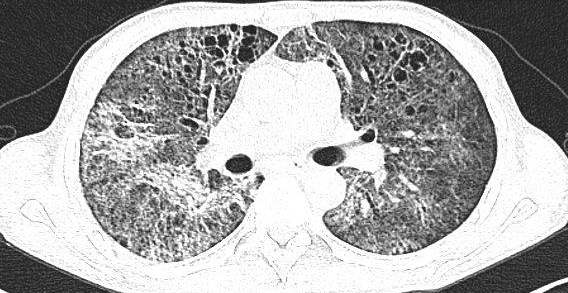

1.1  一般资料  选取 2018 年 1 月至 2020 年 12 月本院收治的 104 例艾滋病伴肺孢子菌肺炎患者为研究对象。纳入标准:符合《艾滋病诊疗指南》[4]和《肺孢子菌肺炎诊断与治疗》[5] 中相关诊断标准;人类免疫缺陷病毒(HIV )抗体阳性;伴低氧血症;胸部 X 线检查可见双肺从肺门开始的弥漫性网状结节样间质性浸润征象,有时为磨玻璃状

1.3  观察指标  ( 1)比较两组临床疗效。显效:    低热、干咳及呼吸困难等临床症状基本消失,复查胸部 CT 显示炎性病灶吸收 >50%;好转:低热、干咳及呼吸困难等临床症状明显改善,复查胸部CT显示炎性病灶吸收, 但未超过 50%;无效:低热、干咳、呼吸困难等临床症状与胸部 CT 检查结果无明显变化。总有效率 = (显效 + 好转)例数 / 总例数 ×100%。(2)比较两组治疗前后实验室指标 [ 白蛋白(ALB)、乳酸脱氢酶(LDH)] 水平。采集患者空腹静脉血 4 mL,常规离心取血清,以酶联免疫吸附法检测 ALB、LDH 水平。(3)比较两组治疗前后血气指标 [ 动脉血氧分压(PaO2 )、血氧饱和度(SaO2 )] 水平, 采用血气分析仪检测。(4)比较两组不良反应发生率。